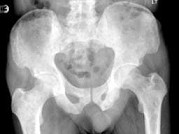

- 单项选择题男,77岁, 全身性骨痛,夜间加重, 贫血,PSA大于100, 结合图像,最可能的诊断是 ( )

A、成骨性骨转移

B、多发性骨髓瘤

C、慢性化脓性骨髓炎

D、骨肉瘤

E、以上都不是